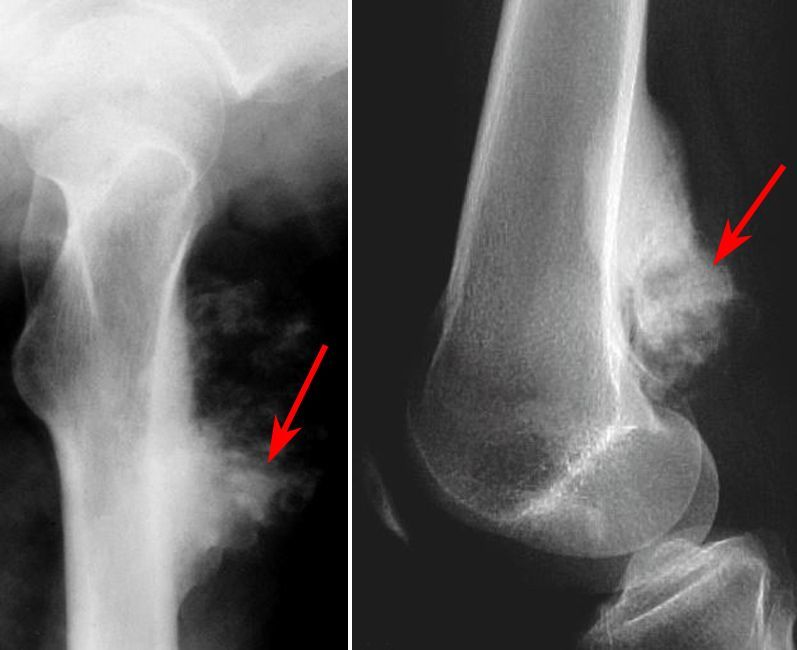

Used in osteosarcoma

Hodgkins + Ewings Sarcoma